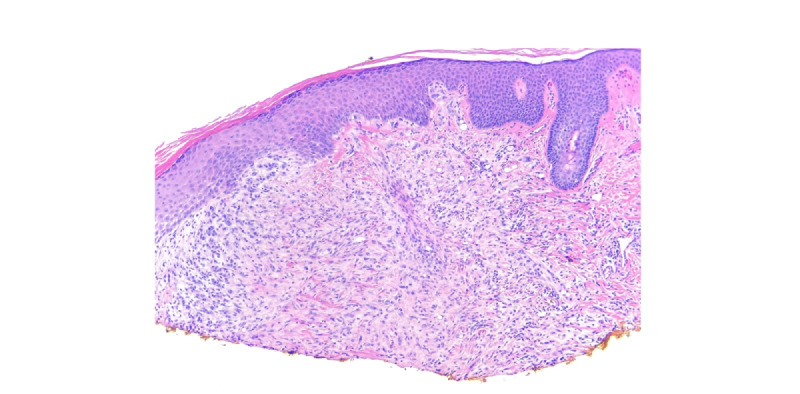

Epithelioid hemangioendothelioma (EHE) is a rare vascular tumor with metastatic potential. EHE can have single- or multiorgan involvement, with presentations ranging from asymptomatic disease to pain and systemic symptoms. The extremely heterogeneous clinical presentation and disease progression complicates EHE diagnosis and management. We present the case of a 24-year-old woman with two periauricular erythematous papules, leading to the discovery of metastatic EHE through routine biopsy, despite a noncontributory medical history. Histology revealed the dermal proliferation of epithelioid cells and vacuoles containing red blood cells. Immunohistochemistry markers consistent with EHE solidified the diagnosis. Although extremely rare, prompt diagnosis of EHE is essential for informed decision-making and favorable outcomes. Key clinical and histopathological findings are highlighted to aid dermatologists in diagnosing and managing this uncommon condition.

上皮样血管内皮瘤(EHE)是一种罕见的血管肿瘤,具有转移潜力。EHE可累及单个或多个器官,表现为无症状、疼痛和全身症状。临床表现和疾病进展的异质性极高,使 EHE 的诊断和治疗变得复杂。我们介绍了一例 24 岁女性的病例,她有两个耳周红斑丘疹,尽管病史不详,但通过常规活检发现了转移性 EHE。组织学检查发现真皮层增生的上皮样细胞和含有红细胞的空泡。与 EHE 一致的免疫组化标记物明确了诊断。尽管 EHE 极其罕见,但及时诊断对于做出明智决策和取得良好疗效至关重要。本文强调了关键的临床和组织病理学发现,以帮助皮肤科医生诊断和处理这种不常见的疾病。